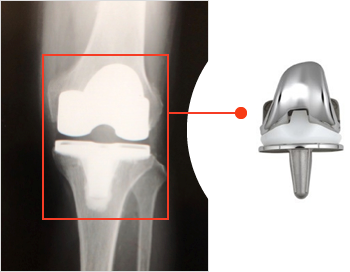

変形性膝関節症

変形性膝関節症は中高齢者の膝痛の最も多い原因疾患であり関節内の軟骨や半月板が変性、摩耗して骨変形をきたします。まずは外来で保存療法(投薬や運動療法や関節注射など)を行っています。保存療法にて改善が得られない場合は変形の程度や年齢によって治療方法を決めており当科では関節鏡視下での滑膜・半月版切除術や高位脛骨骨切り術や全人工膝関節置換術(図4)を行っています。

図4

全人工膝関節置換術